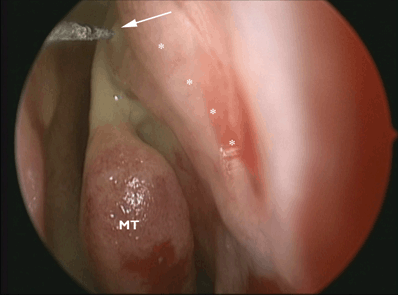

Figure 25-1. Endoscopic view of the injection of the insertion of the middle turbinate. (MT : Middle Turbinate. White arrow points to injection at insertion of middle turbinate. White asterisk show sites of injection along the frontal process of the maxilla). Using a nasal speculum and a headlight, the lateral wall of the nose is infiltrated in the area of the uncinate process and along the frontal process of the maxilla. The insertion and the turbinate itself are also infiltrated, and the area above can also be injected. The nose is packed gently with neurosurgical cottonoids soaked in lidocaine 4% with phenylephrine 0.25%. When surgery is performed under local anesthesia, the packing should include the opening of the nostril to ensure proper anesthesia of the tip of the nose. If this is still sensitive at the time of surgery, a small infiltration of the mucosa of the septum in this area can be done. When surgery is performed under local anesthesia, an infiltration of anesthetic is delivered to the medial canthal area, lacrimal sac area, and the anterior ethmoidal nerve from the orbital side. This step is not necessary under general anesthesia.